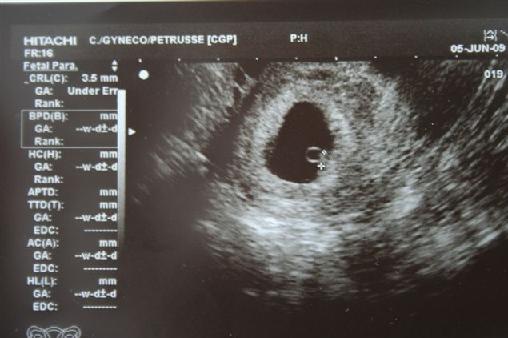

6hetes Ultrahang Nlc

Mi Az A Petezsak

Szivdobbanas Babuci